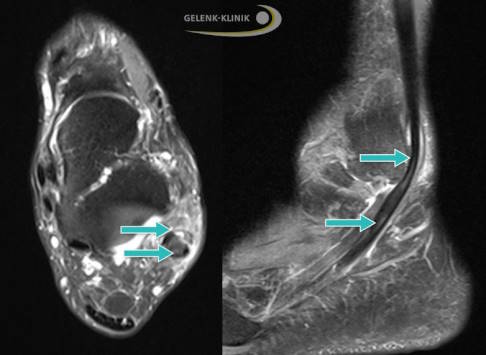

Der Längsriss der kurzen Peronealsehne heißt Peroneus-Split-Syndrom. Der Riss tritt typischerweise im Bereich hinter dem Außenknöchel auf und kann sowohl durch akute Verletzungen als auch durch chronische Sehnenschäden entstehen. Betroffene geben meist Schmerzen an der Außenseite des Sprunggelenks an, vor allem bei Belastung und Bewegung des Fußes. Oft kommt es dort auch zu Schwellungen, manchmal auch zu Schnappgeräuschen wie bei der Subluxation der Peronealsehne.

Bei allen Peronealsehnenrissen ist zu beachten, dass diese häufig mit anderen Erkrankungen zusammen auftreten. Dazu gehören die chronische Tenosynovitis, schwere Umknicktraumen, Frakturen oder eine chronische seitliche Instabilität des Sprunggelenks.

Dabei hat die DVT mehrere Vorteile: Sie ist nicht nur strahlungsärmer als das konventionelle Röntgen. Mit ihr lassen sich dreidimensionale Bilder anfertigen, auf denen man die Knochenoberfläche, die Gleitrinne der Sehnen und eventuelle Knochenerhebungen gut erkennen kann. Häufig wird auch eine Kernspintomographie durchgeführt. Sie ermöglicht eine besonders gute Beurteilung der Sehne und des umliegenden Gewebes. Risse, Luxationen und Entzündungen der Sehne können damit gut unterschieden werden.